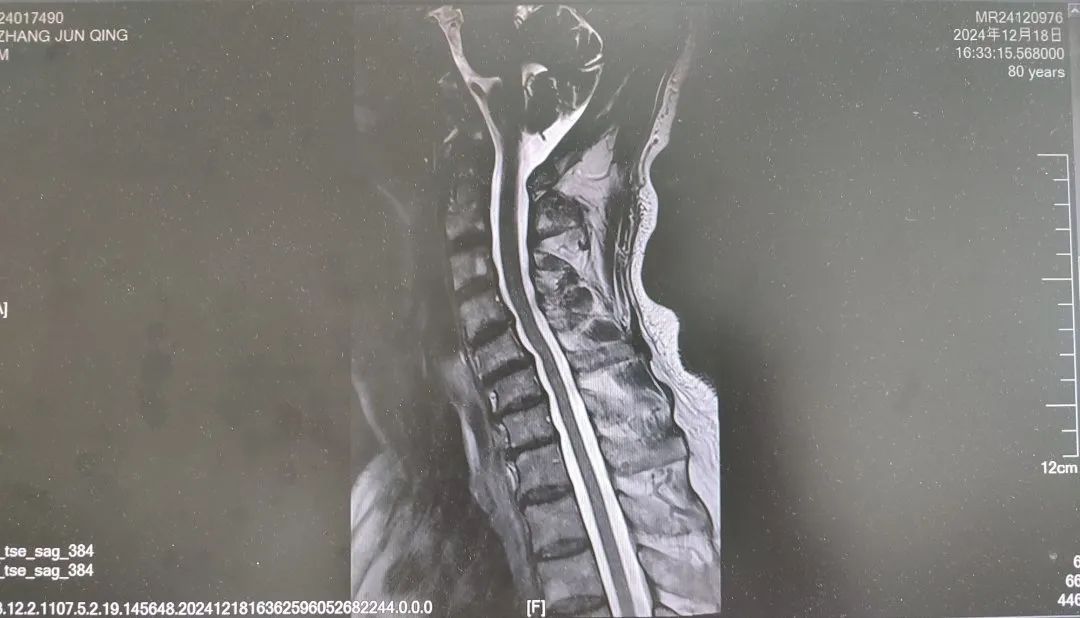

内容提要 很多人都想拥有纤细、健美的双腿,尝试多种健身方法,效果却始终不理想。然而社会上大约有万分之四的人,他们不用减肥,双腿就会慢慢“瘦”下来,如倒置的香槟酒瓶,医学中称之为“鹤腿”。不过这并非自愿,而是源于一种名为“腓骨肌萎缩症”的罕见疾病。近日,市二院神经内二科赵智江主任团队就帮助一位受腓骨肌萎缩症困扰4年之久的患者明确了病因。 #01 “鹤腿”多年不明病因 竟是罕见病作祟 患者80岁,四年前无明显诱因出现步态异常,行走困难,起初以为是劳累所致,并未过多在意。然而,近一年来症状逐渐加重,双下肢膝关节以下麻木、发凉,行走时右下肢有甩脚动作,呈跨阈步态,右足趾背屈不能,同时存在站立不稳、不能蹲下等症状,严重影响日常行走。这一年间,他辗转市内多家医院,经历了无数次的检查和咨询,却始终未能得到确切诊断。 近日,患者经多方打听,来到了以诊治神经疑难病为特色的市二院神经内二科。入院后,赵智江主任为患者进行了细致入微的查体,发现患者双侧大腿下三分之一处及小腿肌肉萎缩。进一步完善头颅、颈椎及胸椎核磁的检查,由于患者存在跨阈步态,结合检查结果,初步考虑为腓总神经麻痹。 头颅、颈椎核磁回报后,基本上排除了神经根的疾病和脊髓疾病。肌电图结果提示四肢周围神经受累,右侧腓总神经损伤更重,修正诊断为周围神经病。然而,周围神经病存在多种病因,需进一步查找病因。赵智江主任结合患者双下肢肌肉萎缩情况,排除其它病因导致的周围神经病,最终明确诊断为腓骨肌萎缩症。 头颅核磁影像 颈椎及腰椎核磁影像 随后,中国医科大学附属第一医院神经内科著名专家何志义教授及辽宁名医、市二院卒中中心主任闵连秋教授在查房时同样肯定了腓骨肌萎缩症的诊断。 腓骨肌萎缩症是一组具有高度临床和遗传异质性的周围神经单基因遗传病,以慢性进行性四肢远端肌无力肌萎缩、末梢型感觉障碍、腱反射减退或消失和高弓足等骨骼畸形为主要临床特征,多为儿童和青少年期起病。该患者老年起病,极为罕见!目前,腓骨肌萎缩症无特效治疗药物,主要以支持治疗为主。今后,患者只要在康复医师的指导下,根据神经损害范围进行合理的康复锻炼,就能保持较好的活动能力,提高生活质量。 市二院神经内二科赵智江主任团队拥有丰富的神经系统疑难疾病诊治能力,曾帮助大量饱受罕见病困扰多年的患者明确了诊断。随着诊疗水平的持续精进,神经内二科将为更多患者提供精确诊断及治疗,为更多的神经疑难疾病明确诊断,为患者带来福音。 #02 人民医院 人民名医 赵智江 主任医师 副教授 ·葫芦岛市第二人民医院神经内二科主任 ·中国卒中学会高级会员 ·中国老年保健医学研究会老年脑血管病分会委员 ·北京神经内科学会脑小血管病学会委员 ·安徽医药杂志审稿专家 专业特色:以脑血管病为核心研究方向,擅长各类神经系统疾病的诊疗,尤其在脑血管病、帕金森综合征、头晕、头痛、癫痫、重症肌无力以及中枢神经系统脱髓鞘等神经系统疑难、危重疾病的诊疗方面积累了丰富的临床经验。主持多项重要科研项目,并将最新的科研成果应用于临床实践,撰写十余篇论文著作。